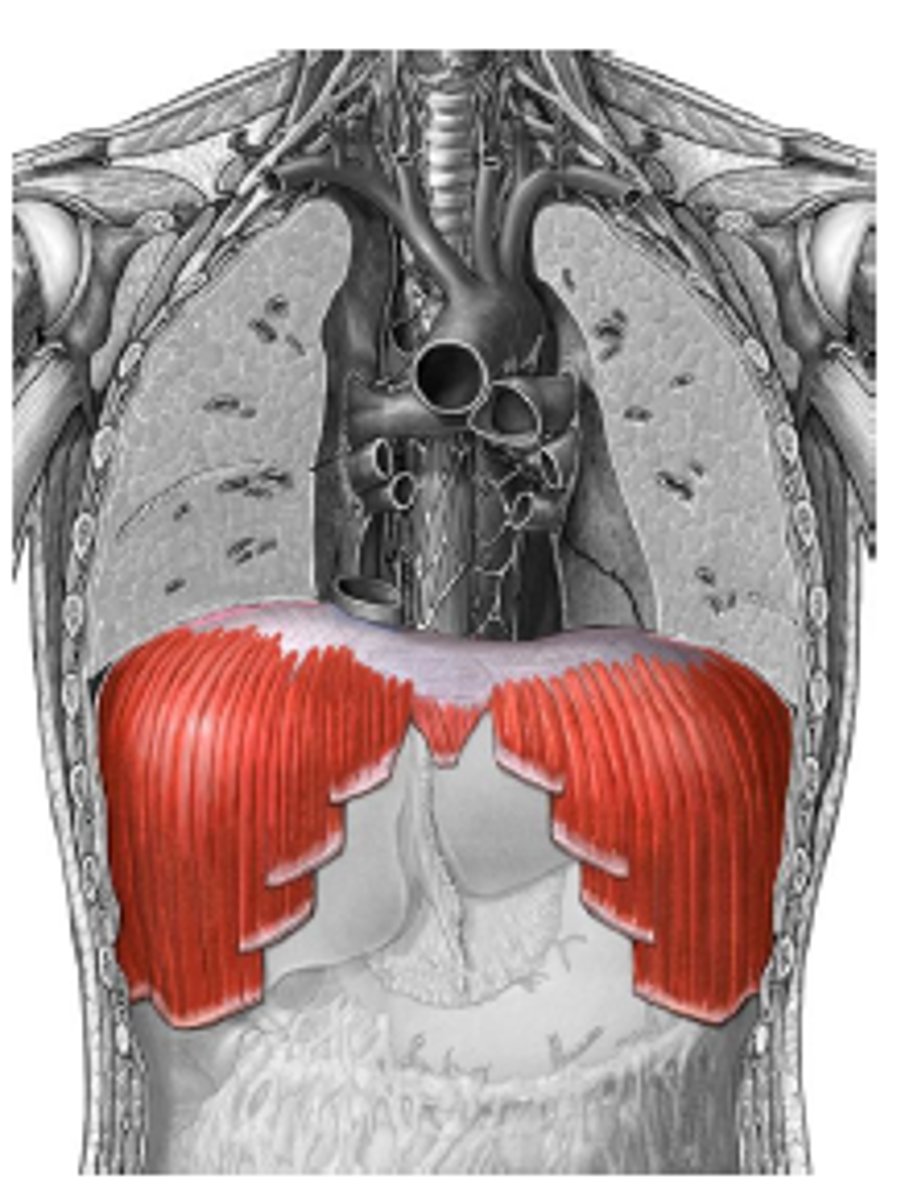

thoracic diaphragm

separates the thoracic and abdominal cavities